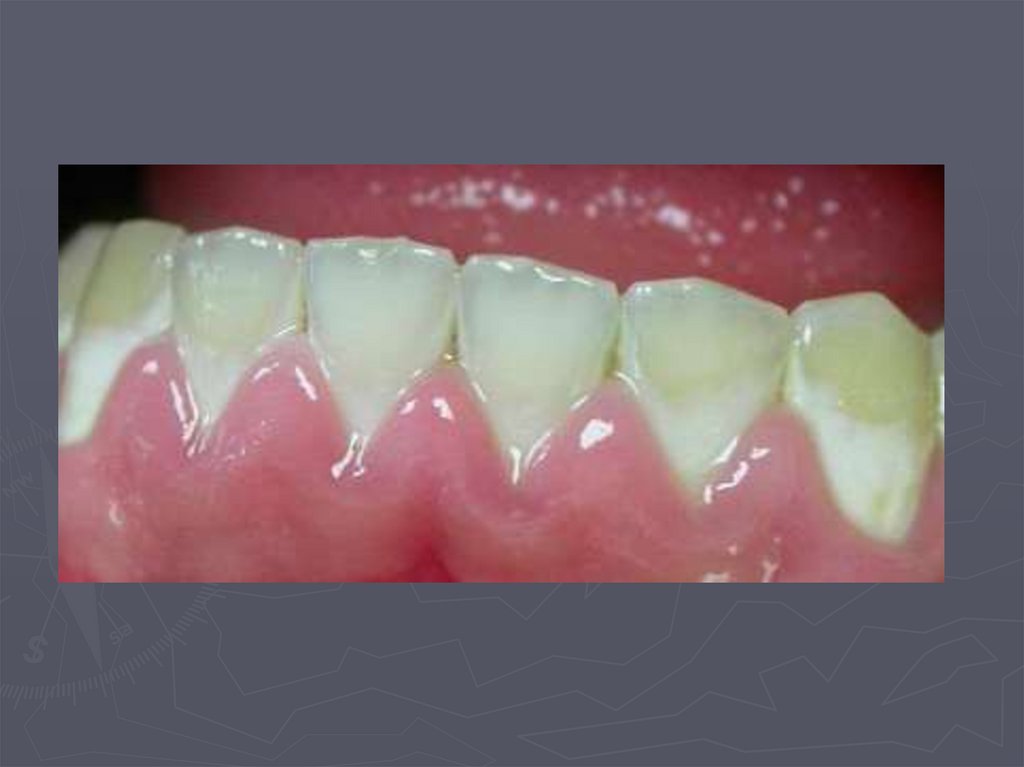

Начальный кариес (кариес в стадии пятна)

19. КЛИНИЧЕСКАЯ КАРТИНА НАЧАЛЬНОГО КАРИЕСА при компенсированной форме:

► заболевание протекает бессимптомно;

► участок поражения может быть покрыт зубным

налетом;

► в участке поражения пятно меловидное или

пигментированное;

► эмаль пятна матовая;

► поверхность пятна гладкая, плотная;

► зондирование безболезненно;

► на температурные раздражители не реагирует.

20. КЛИНИЧЕСКАЯ КАРТИНА НАЧАЛЬНОГО КАРИЕСА при декомпенсированной форме:

►пятно белого или светло-коричневого

цвета;

► пятно не имеет четких границ;

► эмаль пятна тусклая;

► поверхность пятна шероховатая ;

►при зондировании эмаль неплотная.